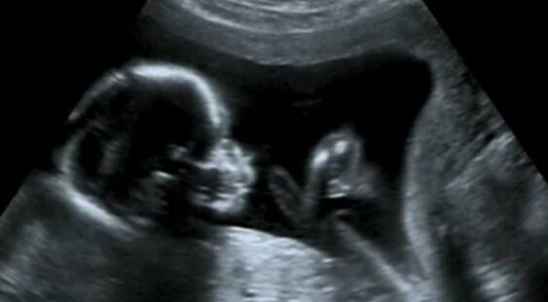

1. 妇产科:COS系统B超在妇产科的应用十分广泛,如胎儿畸形筛查、孕期监护、妇科疾病诊断等。